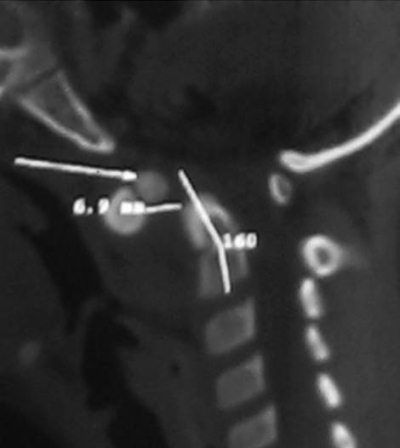

Б – КТ сагиттальная плоскость. "Зубовидная кость" величиной в 1/3 эпистрофия интерполирована в сустав Крювелье. Пространство для спинного мозга (SAC) резко сужено.